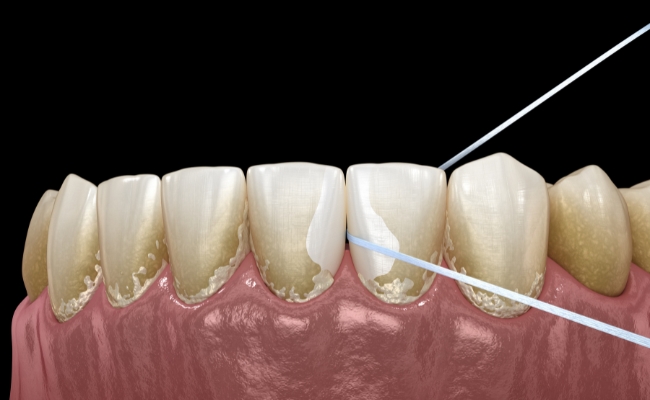

- Mezizubní kartáčky nebo nit – plak se hromadí i mezi zuby, kam klasický kartáček nedosáhne.

Skutečný zubní kámen, který již mineralizoval, nelze bezpečně odstranit doma. Domácí pokusy mohou poškodit sklovinu nebo dásně. Proto doporučujeme profesionální odstranění zubního plaku a kamene u dentální hygienistky pomocí ultrazvuku, kyret nebo pískování.